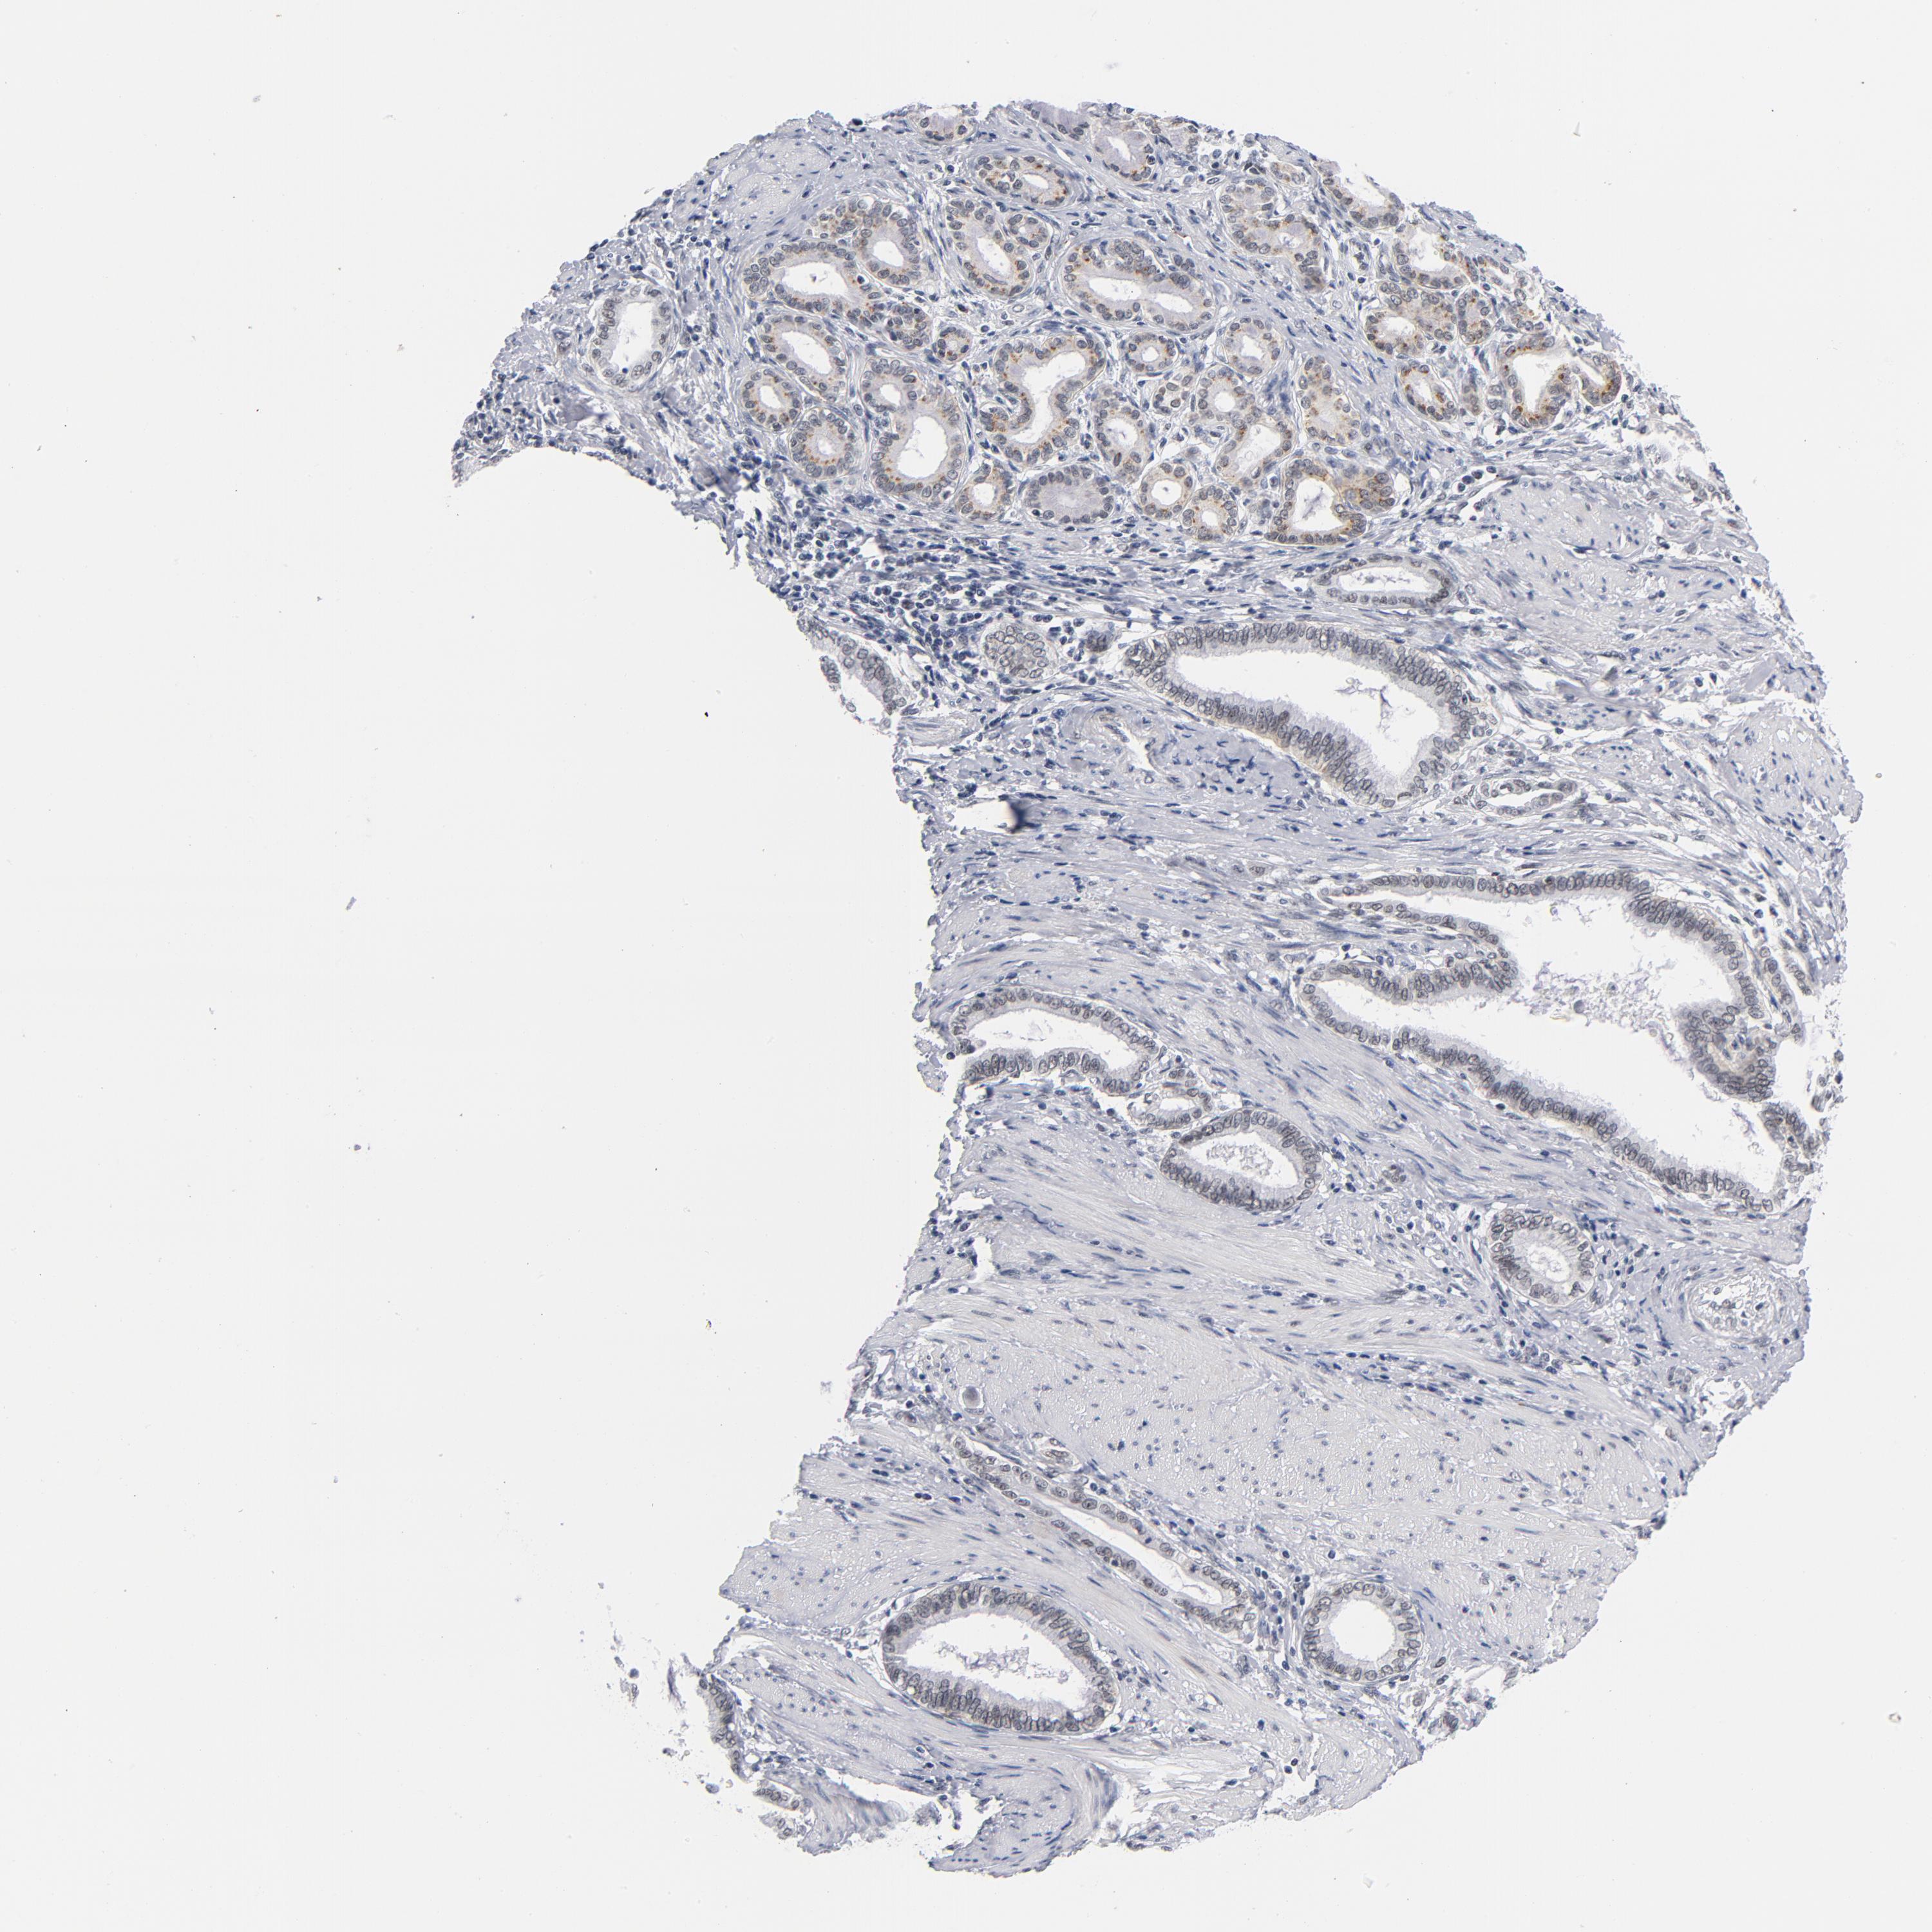

PANCREATIC CANCER - Protein expressioni

A mouse-over function shows sample information and annotation data. Click on an image to view it in a full screen mode. Samples can be filtered based on level of antibody staining by selecting one or several of the following categories: high, medium, low and not detected. The assay and annotation is described here.

Note that samples used for immunohistochemistry by the Human Protein Atlas do not correspond to samples in the TCGA dataset.

Antibody stainingi

Antibody staining in the annotated cell types in the current human tissue is reported as not detected, low, medium, or high, based on conventional immunohistochemistry profiling in selected tissues. This score is based on the combination of the staining intensity and fraction of stained cells.

Each image is clickable and will lead to virtual microscopy that enables deeper exploration of all samples and also displays staining intensity scores, fraction scores and subcellular localization as well as patient and tissue information for each sample.

Antibody HPA028814

Antibody CAB004322

Staining

High

Medium

Low

Not detected

Intensity

Strong

Moderate

Weak

Negative

Quantity

>75%

75%-25%

<25%

None

Location

Nuclear

Cytoplasmic/membranous

Cytoplasmic/membranous,nuclear

Adenocarcinoma, NOS

Adenocarcinoma, metastatic, NOS